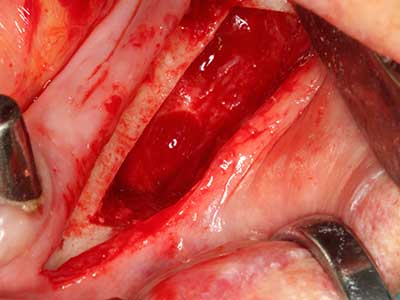

Piezosurgery has additional advantages when harvesting bone blocks. In addition to the high precision with osteotomy described above, the use of the thin saw tips specifically minimizes loss of material. Greater loss of material during harvesting can be expected with the thicker instrument tips, particularly when using Lindemann drills (Lakshmiganthan, Gokulanathan et al. 2012). The basal separation, which is necessary particularly for retromolar block transplants, is simplified by specially designed rectangular saws, with the result that piezosurgery is viewed as a precise, simple and safe procedure for harvesting retromolar bone blocks (Happe 2007) (Fig. 1-12).